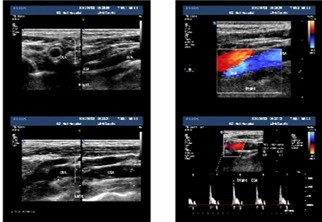

一般情况介绍 患者张XX,男,69岁,因“跌倒致左髋疼痛、活动障碍6天”入院。既往史:“糖尿病”15年,一直服“拜糖平”、“二甲双胍”治疗,血糖控制在 7~15mmol/L之间。高血压病史4年,最高达180/90mmHg,未系统服药治疗。曾有脑梗塞病史,2月前因“双侧颈动脉粥样硬化、右颈内动脉中 度狭窄”行右颈动脉支架成形术,现服用波立维、拜阿斯匹林联合抗血小板治疗。查体:左髋部无肿胀、瘀斑,关节活动受限,叩痛、压痛(+),左下肢外旋 60°畸形。双足多处皮肤破溃坏死,创面干燥,右足足背动脉搏动不明显。影像学资料:骨盆正位、左侧髋关节侧位示“1、左侧股骨颈骨折;2、骨盆骨质疏 松”(图1、2)。颈动脉超声示“双侧颈动脉粥样硬化伴多发斑块”(图3)。下肢动脉彩超示“双下肢动脉粥样硬化闭塞症声像;右侧胫前及左侧胫前、足背、 胫后动脉广泛狭窄(中-重度);右足背动脉狭窄(轻度)” (图4)。下肢静脉彩超示“左下肢深静脉血栓栓塞声像:左侧腓静脉(后一条)及左小腿多发肌间静脉完全栓塞。双侧股静脉及腘静脉血流缓慢。余双下肢深静脉 及大隐静脉近段未见明显异常声像” (图5)。心脏彩超示“主动脉硬化、主动脉瓣退行性变;左房增大,心内血流未见明显异常;左室收缩功能未见异常,舒张功能减退”。血生化指标:凝血四项示 “纤维蛋白原6.64g/L”,D-二聚体“1499ng/ml”。结合患者病史、体征及辅助检查,诊断“1、左股骨颈骨折;2、Ⅱ型糖尿病;3、高血压 病;4、脑梗塞后遗症;5、右颈动脉支架成形术后”。请内分泌科、心血管内科会诊,停用波立维、拜阿斯匹林,行降糖、降压、营养支持等对症治疗。入院后两 周在气管插管全麻下行“左侧人工股骨头置换术”,术程顺利。患者麻醉清醒后即嘱其行双下肢肌肉主动舒缩及膝踝关节屈伸活动,术后12h开始首次应用磺达肝 癸钠2.5mg皮下注射,以后每天以同等剂量皮下注射一次。患者术后5天即可在助行器帮助下下床活动,磺达肝癸钠持续用至10天停止,并防治感染、降糖、 降压、营养支持治疗。治疗期间每日观察患肢是否有肿胀情况,测量双侧大腿及小腿周径并记录。术后两周复查双下肢动静脉彩超,与术前结果相同;行肺部X线片 及CT检查,未见肺动脉栓塞征象。骨盆X线片示人工股骨头置换术后改变,人工假体位置佳(图6)。患者顺利出院,并恢复波立维、拜阿斯匹林联合抗血小板治 疗。

图3 颈动脉超声示双侧颈动脉粥样硬化伴多发斑块